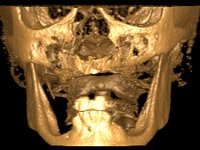

After clinical and radiological evaluation several rehabilitation plans were discussed with the patient. It was decided to extract the remaining lower teeth and do an overdenture retained by two dental implants with the locator attachement system to achieve a better retention and stabilization of the lower denture.

Two dental implants were planned in the CBCT scan, in the area of the inferior canines. The dental extractions were performed and, simultaneously, the alveolar crest was flattened and the implants were placed. Three issues were considered while implant placement: parallelism of the axis, same height of the implant’s neck, and same position in the coronal plan. This 3D insertion is essential to have a good retention of the overdenture in the future. Patient’s removable denture was fixed in the dental lab, to include the extracted teeth, and a soft-tissue relining was done over the healing abutments. After the osseo-integration period, a first impression was done with an open-tray and a doble-mix technique. This dental impression allowed the production of screwed wax-rims and an individual tray for a functional impression. A second impression, final, was done with an individual tray with a monophasic silicone. The occlusal wax-rims were correct in the mouth according to the full denture guidelines. Special care was taken with the occlusal vertical dimension and the support in the soft-tissues. A silicone bite registration material was used to better defined the intermaxillary relations. Teeth set-up was done in the dental lab with the selected tooth color. Due to the fact that the base was screwed to the dental implants, the teeth set-up was functionally evaluated in the mouth. Another silicone bite registration material was used to allow final occlusal adjustments. Finally, the locators were screwed and the retention nylons were selected according to the patient needs.